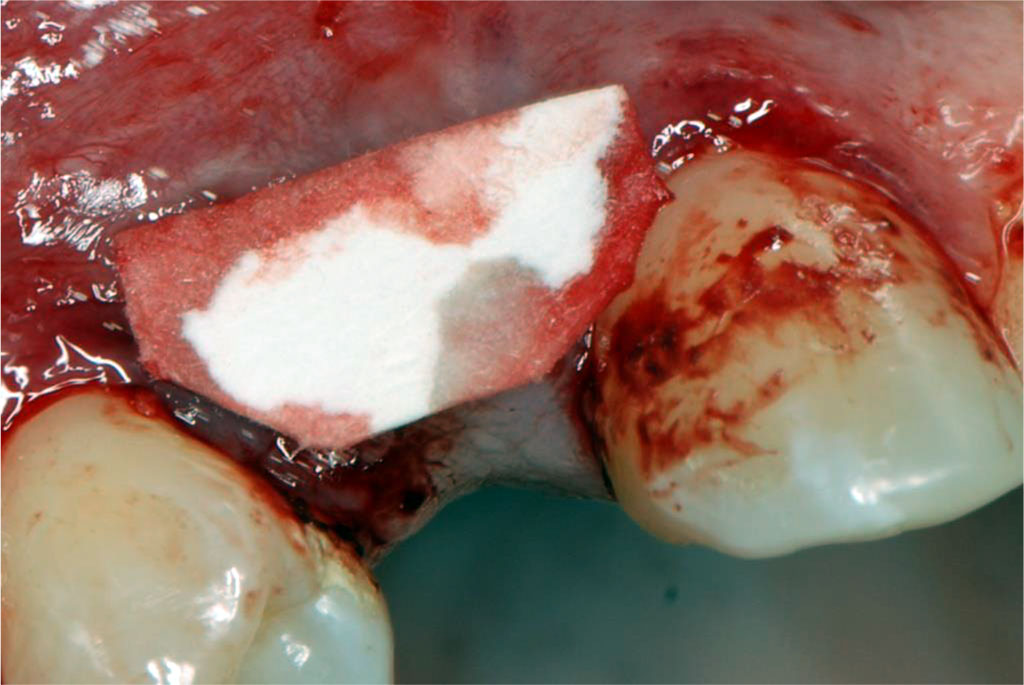

The patient was qualified for peri-implant soft tissue augmentation using the tunnel technique and a subepithelial connective tissue graft (sCTG) taken from the palate. The procedure was discussed, post-operative recommendations were explained and written informed consent was obtained for the procedure. One Shot - 2g of Amoxycyllin was administered 1h before surgery - perioperative antibiotic prophylaxis. Prior to the procedure, the patient had blood drawn from the ulnar vein to obtain Advanced Platelet Rich Fibrin (A-PRF) membranes to secure the donor site located on the palate (Fig.2). Infiltration anaesthesia of the donor site and conduction block anaesthesia of the greater palatal orifice with articaine 1:100000 was administered. With use of preoperatively prepared template (Fig.3), an epithelial-connective tissue graft was harvested from the palate using the free gingival graft (FGG) technique (Fig.4). A larger amount of sCTG was harvested due to the need to simultaneously cover gingival recessions in the left maxillary region. The graft was then de-epithelialised (Fig.5). The donor site wound was secured with an A-PRF membrane and crossed 5-0 non-resorbable mattress sutures (Fig.6). Under infiltration anaesthesia of the recipient site with a 1:100,000 preparation of articaine in area 12-14, a supraperiosteal tunnel was dissected (Fig.7). An sCTG was then inserted into the tunnel (Fig.8) and 6-0 non-resorbable sutures were placed to position and stabilise the graft in the intracoronal position (Fig.9). Oral rinsing with 0.1% chlorhexidine digluconate for 2 weeks, and postoperative instructions were prescribed. Wound toileting was performed at the follow-up visits each time.

Fig.4 Harvesting an sCTG graft from the palate using the free gingival graft technique.

Fig.5 The epithelial-connective tissue graft was de-epithelialized after harvesting, resulting in an sCTG.